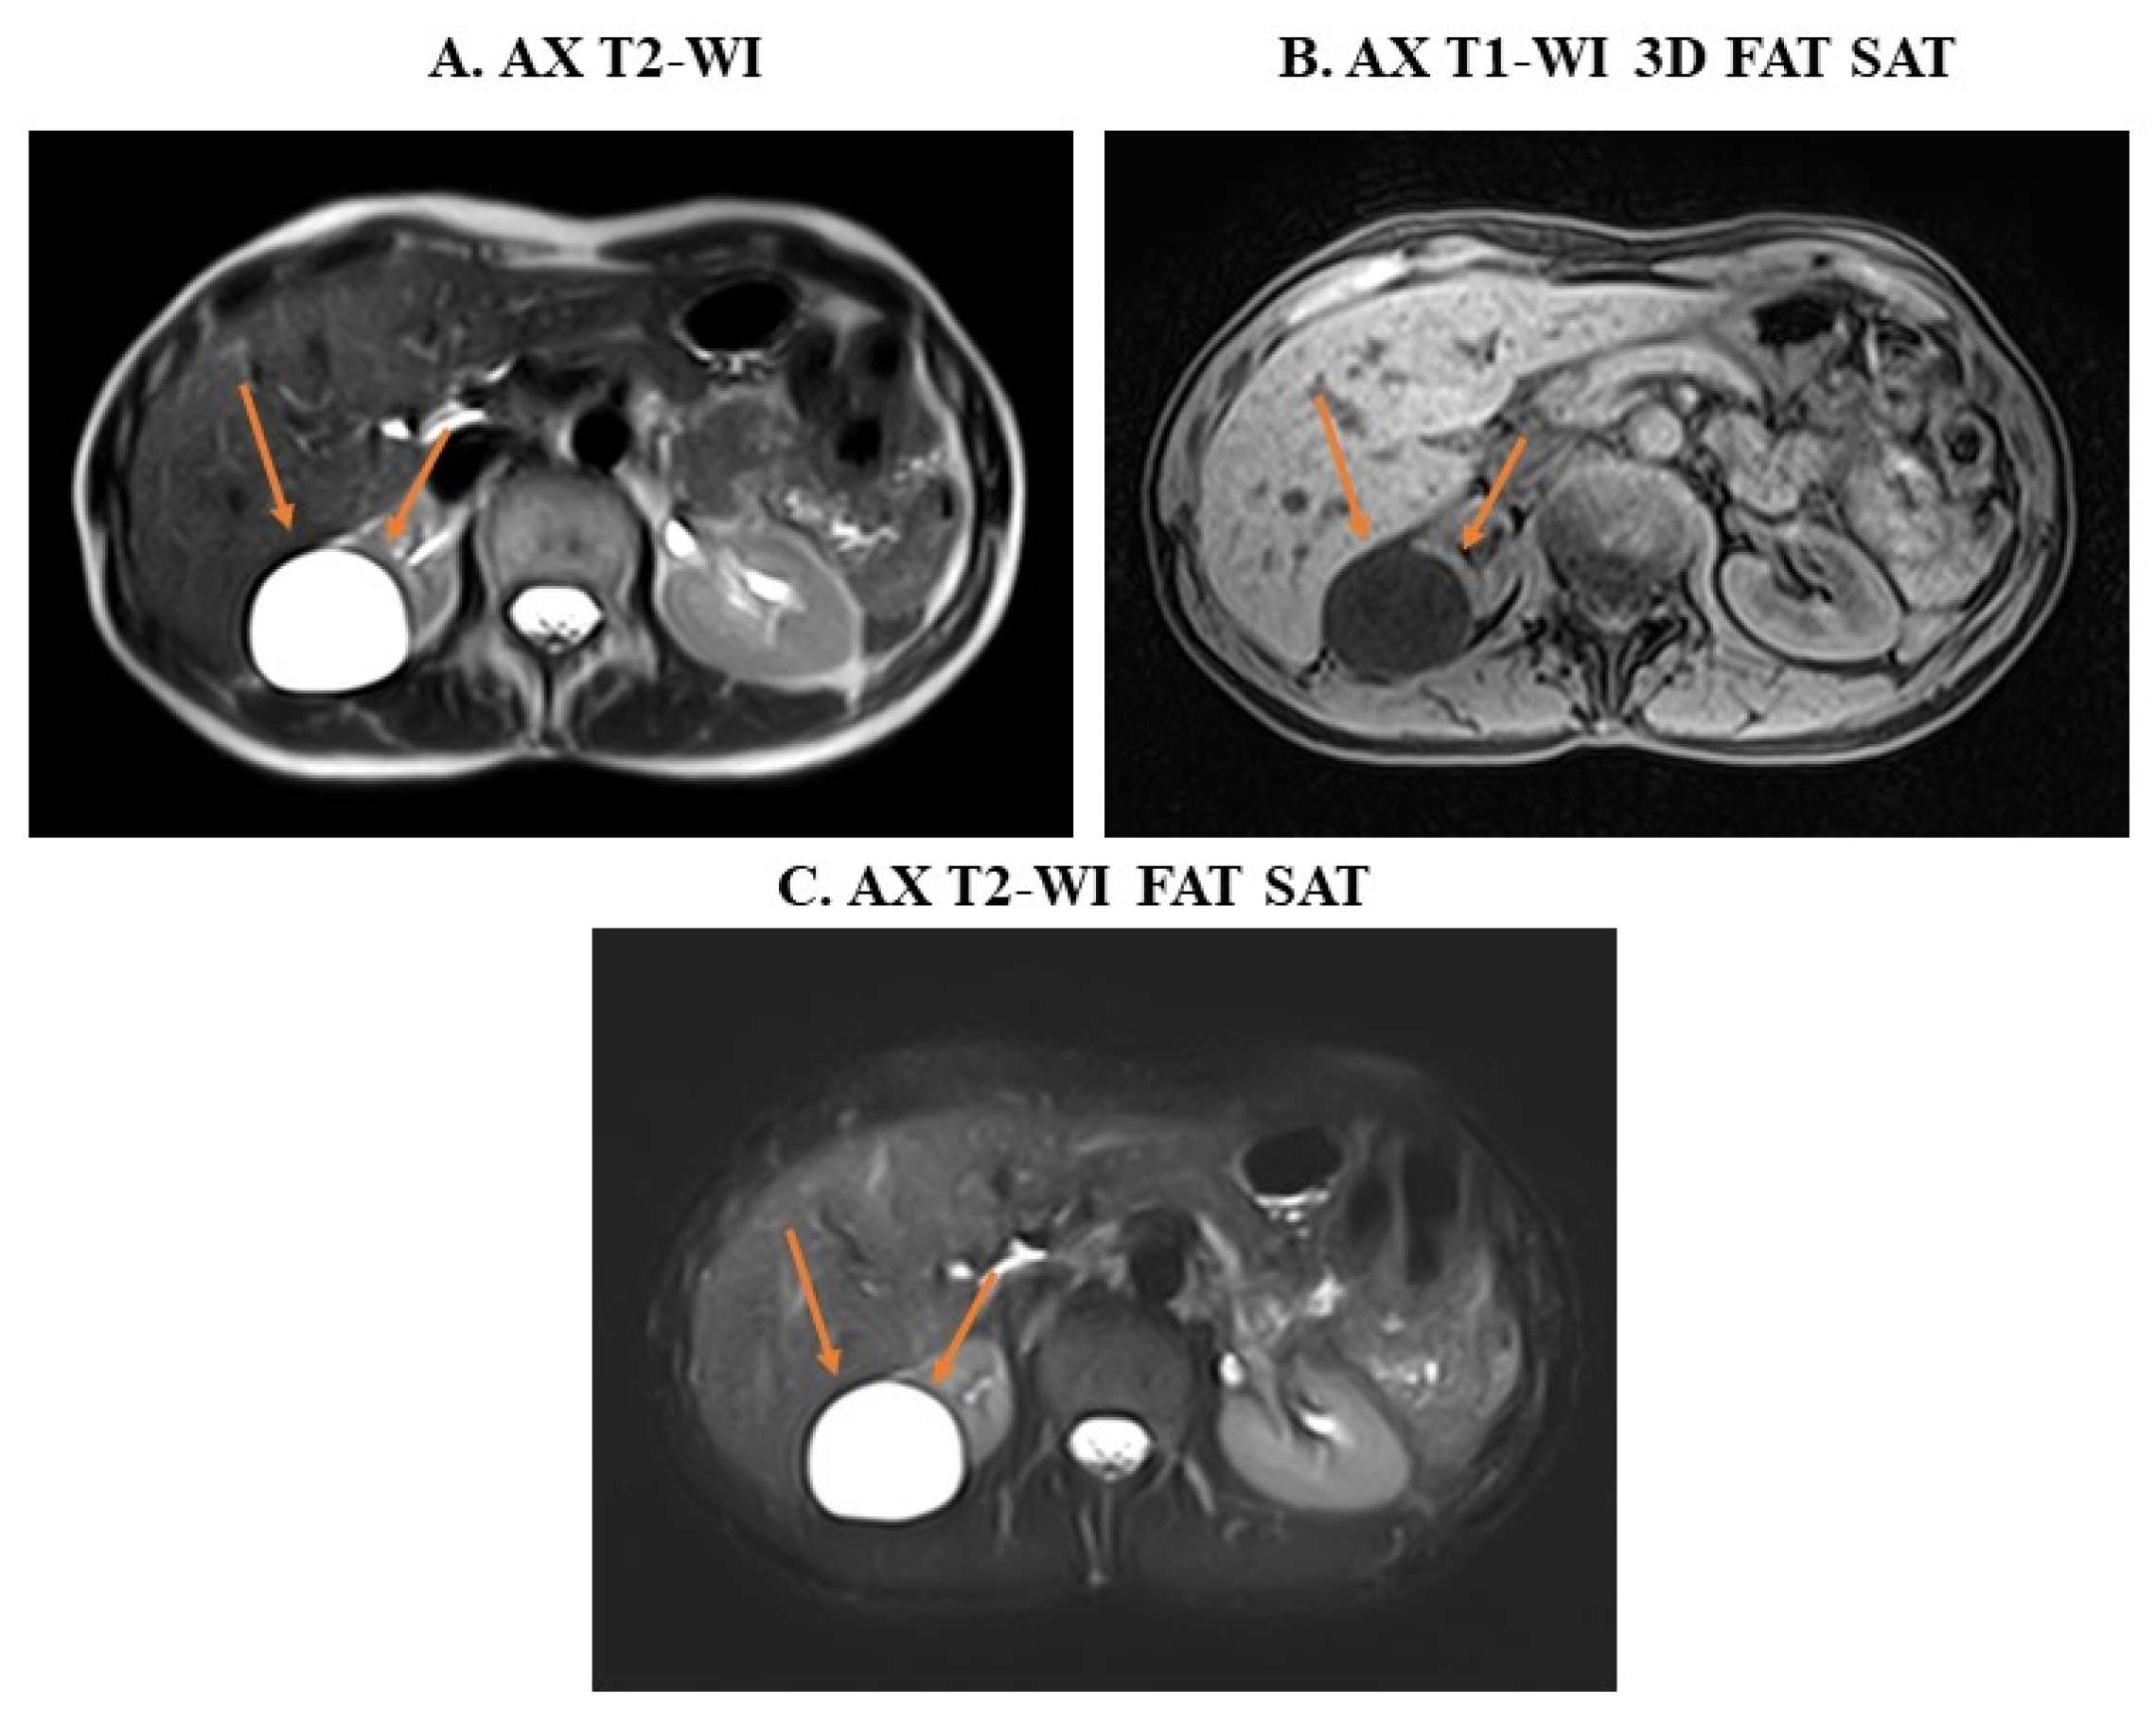

3. Examples of Applications of MRI Sequences in Upper Abdominal Analysis

4.2. Monitoring of Abdominal Lesions from CT to MRI